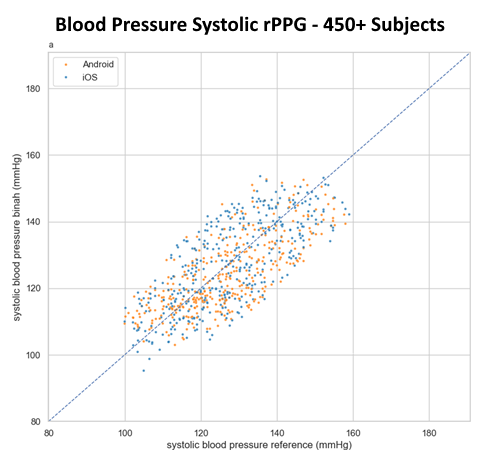

Briah.ai’s technology can measure blood pressure, heart rate, heart rate variability, respiration rate, hemoglobin, and hemoglobin A1C.

How accurate are the measurements provided by Briah.ai?

Our technology meets high accuracy standards and has been validated through extensive research and testing.